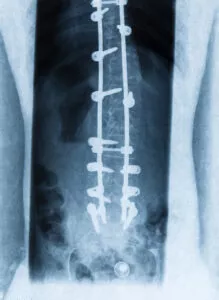

Spinal fusion surgery aims to alleviate back pain by permanently connecting two or more vertebrae in your spine, resulting in a single, solid piece of bone. This procedure eliminates motion between the fused vertebrae, providing stability and reducing pain.

- Screws and Rods: To stabilize the vertebrae while the bone fusion occurs, screws coupled with rods are often utilized. This hardware ensures the vertebrae remain immobilized during the healing process.